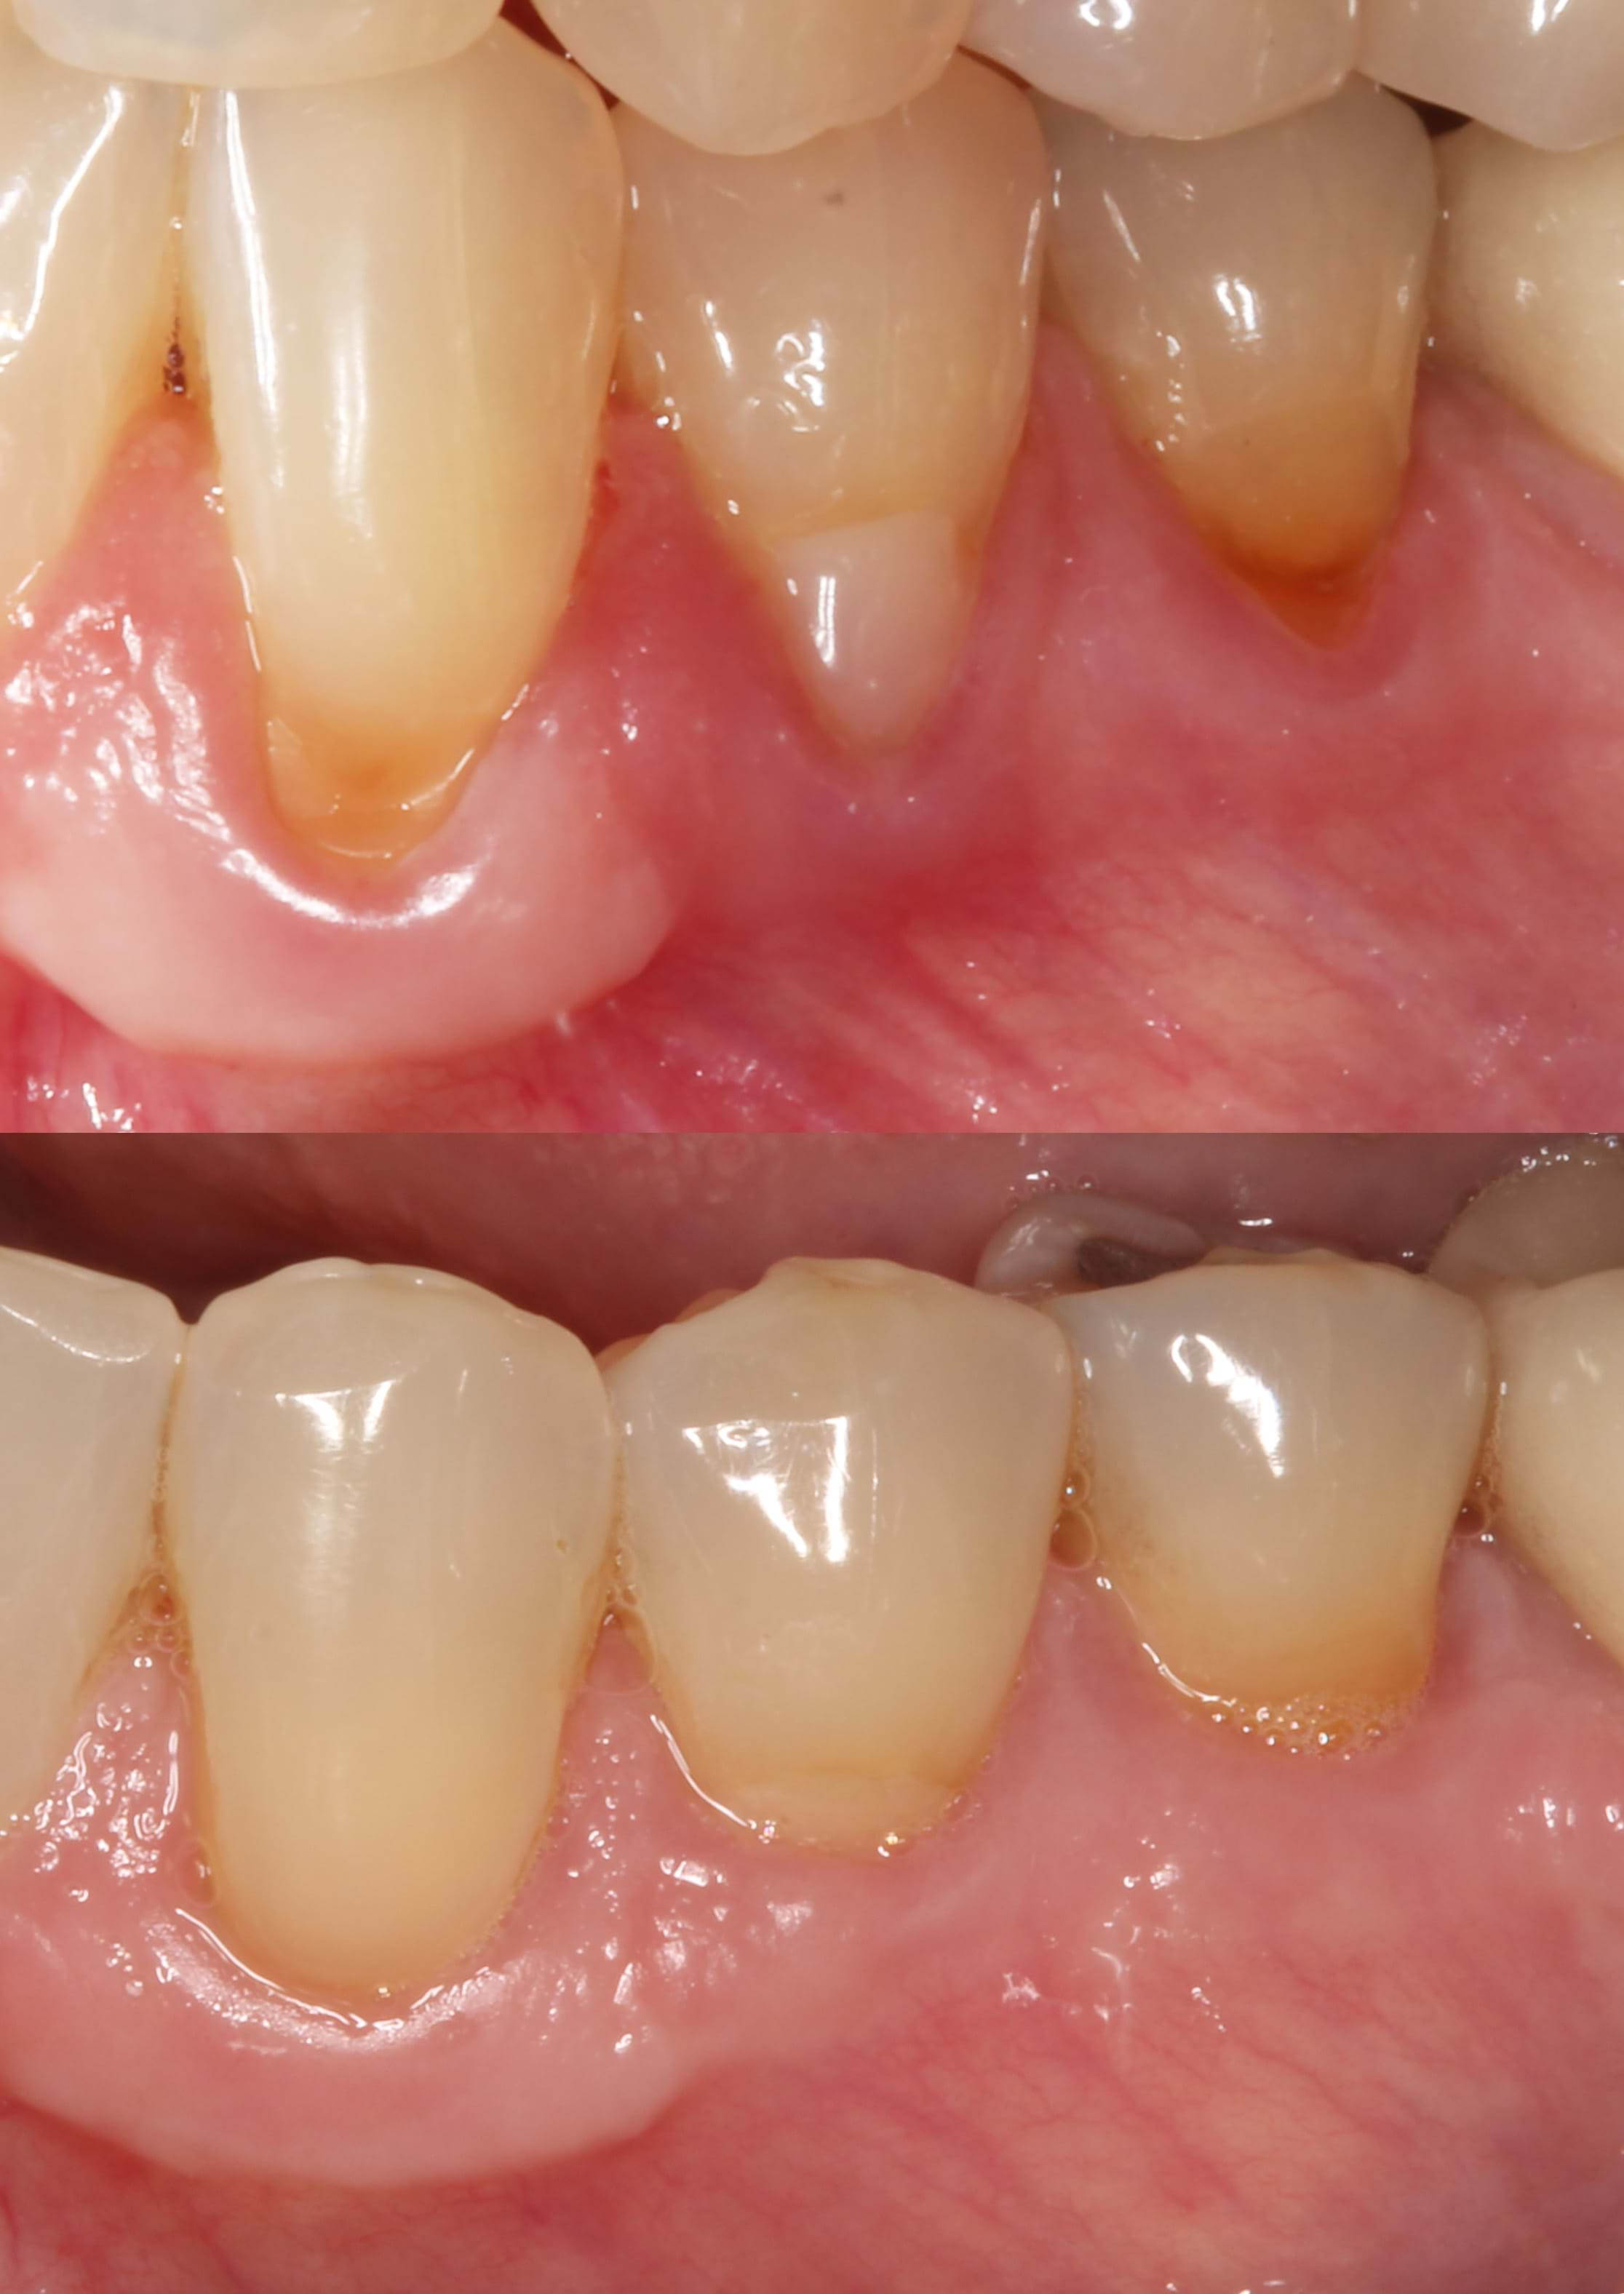

Recession Coverage

Recession coverage can be achieved with periodontal plastic surgery techniques using a Free Gingival Graft (FGG), Connective Tissue Graft (CTG) or using Acellular Dermal Matrix (ADM). If indicated, minimally invasive surgery combined with ADM can be used removing the need to harvest tissue from the patient's palate. This can reduce surgical recovery time with equivalent results.